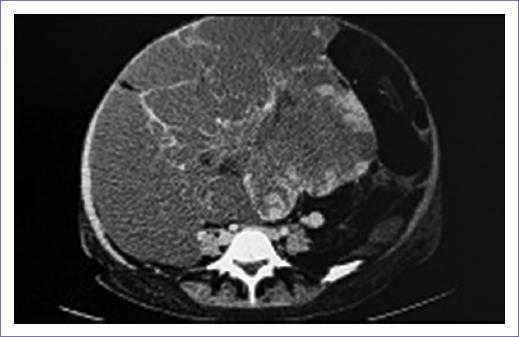

Acude para realización de nueva TC el 27 de enero de 2024, refiriendo dolor a nivel costal derecho, con aumento de perímetro abdominal y anemia, reportando hallazgos de neoformación en retroperitoneo de primario conocido 17 x 20 x 12 cm, engrosamiento focal de la pleura visceral en segmento 6, probable infiltración metastásica (Figs. 1 y 2). A su ingreso, con los siguientes estudios de laboratorio: hemoglobina 6.8 g/dl, hematocrito 24.2%, plaquetas 722,000/ul, leucocitos 10.33 x 103/ul, neutrófilos 75%, calcio 8.4 mg/dl, magnesio 2 mmol/l, sodio 136 mmol/l, potasio 4.1 mmol/l, cloro 96.7 mmol/l, glucosa 102, creatinina sérica 0.4 mg/dl, nitrógeno ureico en sangre 5 mg/dl, tiempo de protrombina 14.7 s, ratio internacional normalizado 1.3, tiempo de tromboplastina parcial 33.9 s, CA 19-9 5.7 Ul/ml, antígeno carcinoembrionario 0.5 ng/ml.

Figura 2 Tomografía axial computarizada abdominal que muestra masa heterogénea con coeficiente de atenuación en rangos lipídicos.